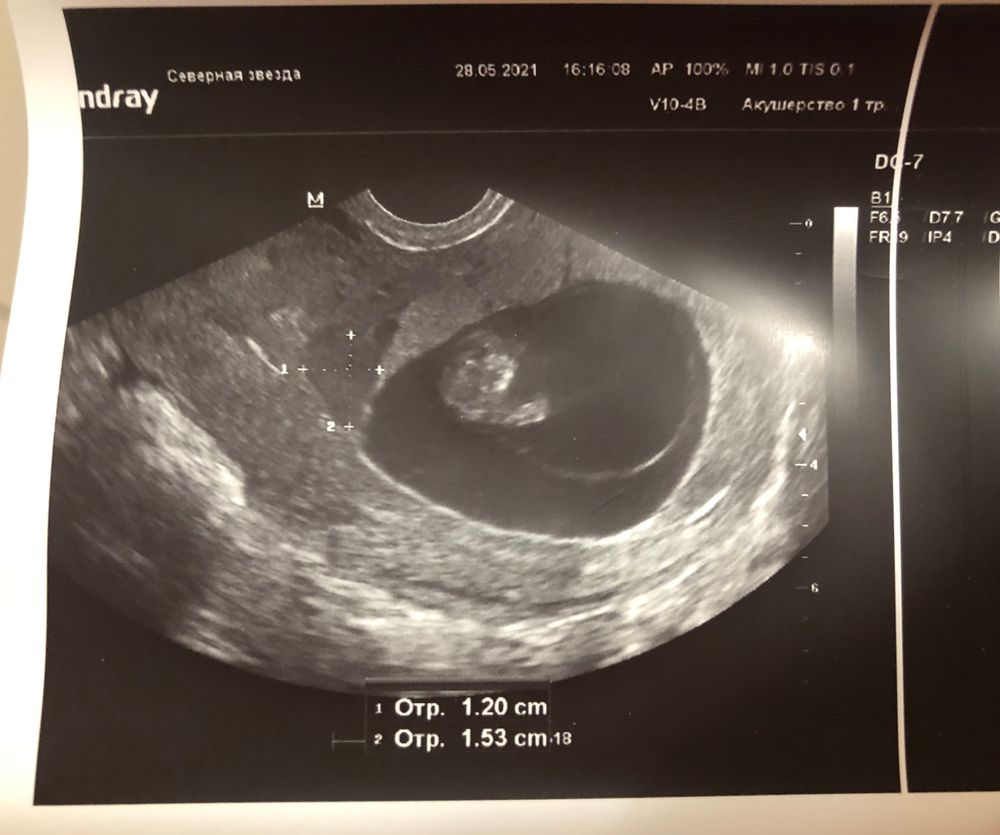

Ретрохориальная гематома

Гематома у Вас маленькая, все хорошо, главное соблюдайте рекомендации. Мне назначали прогестерон в удвоенной дозировке и рекомендовали не поднимать тяжести. Гематомы были с 6 до 14 недель, к 14 неделе рассосалась